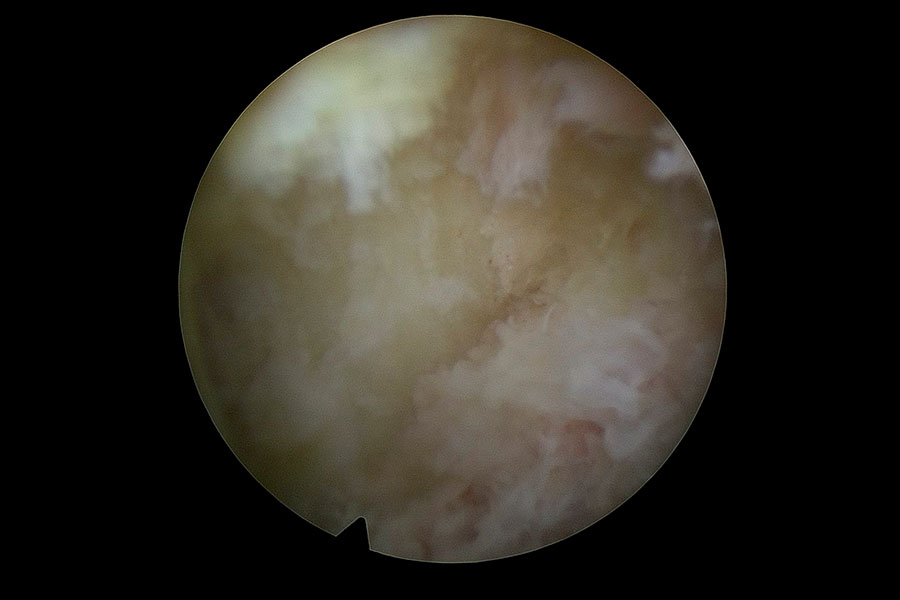

Tras una operación de columna, la paciente presenta una masa blanquecina que se decide retirar mediante técnica avanzada de endoscopia de columna